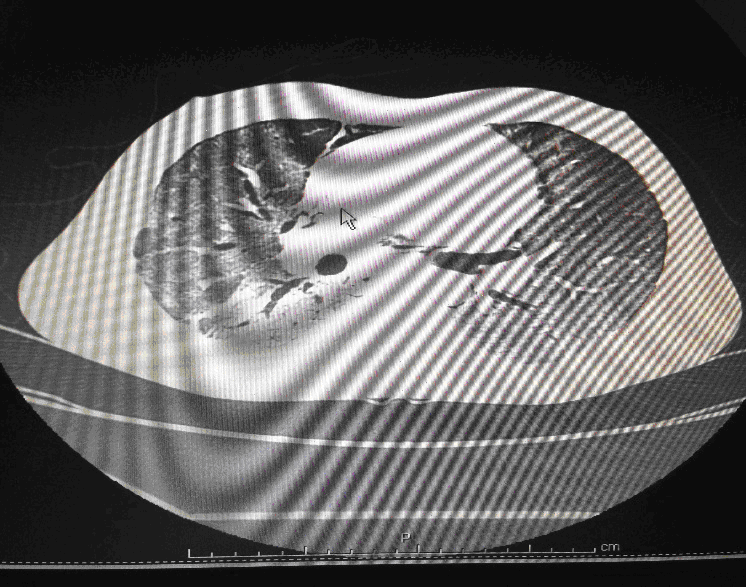

24 year old male, who is a K/C/O Embryonal Ca Testis- S/P Orchidectomy done 6 months back followed by chemotherapy with Bleomycin for 4 cycles, had presented with complains of cough since 1month and fever since 2 weeks. Associated breathing difficulty was also present and cough was productive. On arrival in the ED he was conscious ,oriented and talking .His vitals showed a HR of 125/min, BP of 90/60 and Saturation was 80%in Room Air. His RR was 35/min and was febrile. Work of breathing was greatly increased and bilateral coarse crepitations were present. Blood gases revealed Respiratory Acidosis. A trial of Non Invasive Ventillation (Bi PAP) was tried initially but failed. He was intubated immediately and put on pressure controlled ventilation.IV fluids were started and early antibiotics initiated. Initial CT Thorax showed features suggestive of Brochiolitis Obliterans organizing Pneumonia (BOOP).

Following admission in the Medical ICU, Bronchoscopy was done and started on IV steroids and higher End Antibiotics. His bronchial wash grew ESBL Klebsiella and Pseudomonas. His other organ functions were not deranged. Repeat CT Thorax was taken which showed ground glass opacities, septal thickening, traction bronchiectasis, pleural thickening which was all S/o Drug induced Toxicity-Bleomycin.